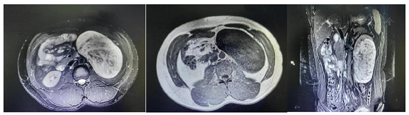

肾脏增强MRI(图2):左肾下极见不规则肿物影,大小约13.8 cm×8.3 cm×15.4 cm,T2WI及T2WI/FS呈混杂高信号,内见多发点片低信号,T1WI/DUAL同相位等低信号,可见点状高信号,对应反相位呈低信号,DWI不均匀高信号,增强扫描皮髓质期肿物强化不明显,内见条状明显强化血管影,实质期及排泄期肿物内见少许散在斑片强化影,肿物边界尚清楚,将左肾实质撑开如杯口样改变,肿物突向肾周间隙生长。CT诊断:左肾下极乏血供肿物,影像学表现不典型,定性困难;结合MRI图像,倾向良性或低度恶性间叶组织来源可能大。